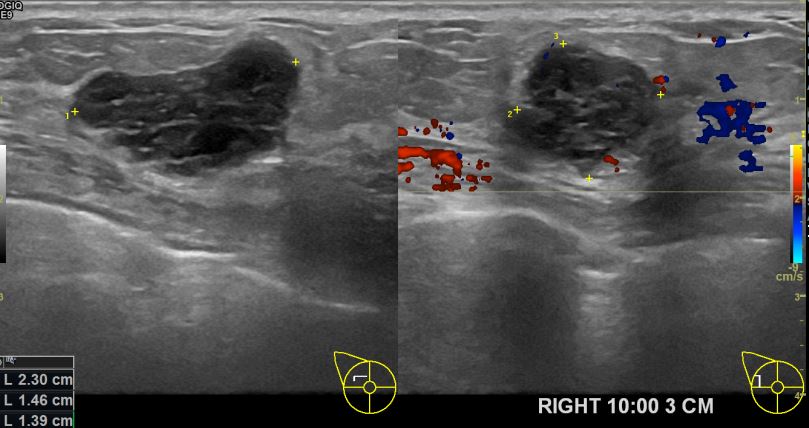

상기환자 우측유방의 만져지는 멍울있어 내원하신 50대 여성분으로 초음파검사후

우측의 의심스러운 혹 조직검사 시행해 유방암진단되었습니다